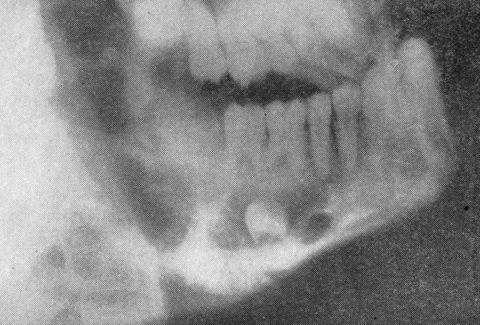

(Слева) На КЛКТ (профильный срез) у этого же пациента визуализируются периостальные наложения, расположенные перпендикулярно кортикальным пластинкам (в виде лучей), а также напластования вновь образованной костной ткани большею размера со стороны щечной и язычной поверхности. В опухоли присутствуют едва различимые кальцинатыв.

(Справа) На аксиальной КЛКТ у этого же пациента определяются периостальные наслоения вновь сформированной костной ткани, расположенные перпендикулярно щечной и язычной кортикальным пластинкам, более выраженные с язычной стороны.

(Слева) Трехмерная реконструкция (вид со стороны язычной поверхности) у этого же пациента позволяет оценить выраженность распространения в нижнюю кортикальную пластинку и дольчатый характер образования.

(Справа) На аксиальной КТ без КУ в верхней челюсти определяется хондросаркома низкой степени злокачественности в виде рентгеноконтрастною образования альвеолярного отростка нижней челюсти справа, имеющего неправильные, грубые края, типичные для злокачественной опухоли. В структуре образования присутствуют точечные обызвествления.